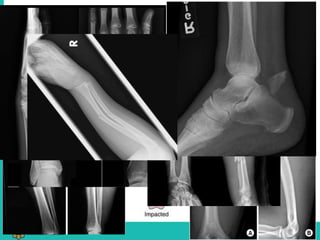

TYPES

1. Transverse – distraction/bending force

2. Oblique – bending, compression

3. Spiral – twisting

4. Impacted – axial loading

5. Comminuted – high energy

6. Greenstick

7. Torus

1. Transverse –distraction/bending force 2. Oblique – bending, compression 3. Spiral – twisting 4. Impacted – axial loading 5. Comminuted – high energy 6. Greenstick 7. Torus